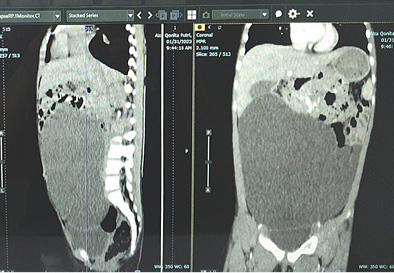

A 4-year-old girl reported having a abdominal distension for two months, there was no history of abdominal pain, vomiting, fever, and no disorders of respiratory or urinary system. Her growth and development were normal and no family history of similar illness; the anamnesis provided the diagnosis. Abdomen was distended with a 15 cm by 15 cm mass with dull percussion, non-tender smooth surface, well-defined border, movable from side to side in the top border, initially around the pelvic area and later to periumbilical area 1 cm under umbilical (Figure 1). Her blood profile, coagulation profile, albumin level, electrolytes, renal and liver functions tests were normal and no hepatitis B surface antigen was found. CT abdomen with intravenous contrast revealed a large cystic mass lesion (Figure 2) with internal septations, origin from the ovary with extending from the pelvis to the cavum abdomen. Other abdominal organs were normal.

Figure 2. Computed tomography of the abdomen demonstrated a AP 7.10 x LL 15.64 xx CC 14.97 cm cystic mass

It was determined by anamnesis, physical examination, and imaging that the diagnosis was an ovarian cyst. As we continue laparotomy with midline incision from obstetrics department, we revealed a 8x8x10 cm sized cystic mass within the left transverse colon omentum, uterus and both ovaries were normal (Figure 3). We excised the cyst in toto and omentectomy then sent for pathological anatomy and cytology analysis. Instead of an ovarian cyst, we found an omental cyst during the operation (Figure 4), thus we had to conduct an excision and omentectomy and postoperatively achieved favorable results. Pathological examination revealed findings a inclusion cyst containing connective tissue, fat, and muscle. Cytology findings are suggestive for transudative effusion from the cyst and the international system for reporting serous fluid (ascites) cytopathology negative for malignancy (Figure 5). She was discharged three day after.

Omental cysts are rare intra-abdominal tumors in children, which are reported incidence of one in twenty thousand admissions to a children’s hospital and female predominance by a factor of 1.5. Different etiological factors have been reported for development of these masses including a benign proliferation of mesenteric lymphatics, failed fusion of the mesenteric leaves, and deficiency of the lymphatico-venous shunts. The literature contains several of cysts which are definitely congenital, but there are also acquired cysts which have been reported. A female factor were found in our case. Presentation is often with abdominal pain with distention and/or palpable abdominal mass, a very small cyst may be asymptomatic and nonpalpable. Disorders of the respiratory or urinary system, in addition to symptoms caused by compression of the portal vein, are often seen because of cyst enlargement. In our case we found a abdominal distension with palpable mass for two months with no history of abdominal pain, and no disorders of respiratory or urinary system. These cysts are usually diagnosed incidentally by abdominal imaging or discovered as an incidental finding at operation. Since it is a rare condition and there are lack of specific symptoms, a correct pre-operative diagnosis is difficult. Our patient underwent CT scanning, allowing us to locate the cyst precisely and identify its relation to the surrounding tissues, leading to a diagnosis of ovarian cyst at first. In laparotomy, we found a giant omental cyst, not originating from the ovaries, and did an omentectomy to excision the cyst. CT scan shows that the giant abdominal cyst is difficult to identify between omental, mesenteric, and ovarian cysts. Precise identification of stomach cysts is necessary. Also, doctors need to read the CT scan image more carefully.